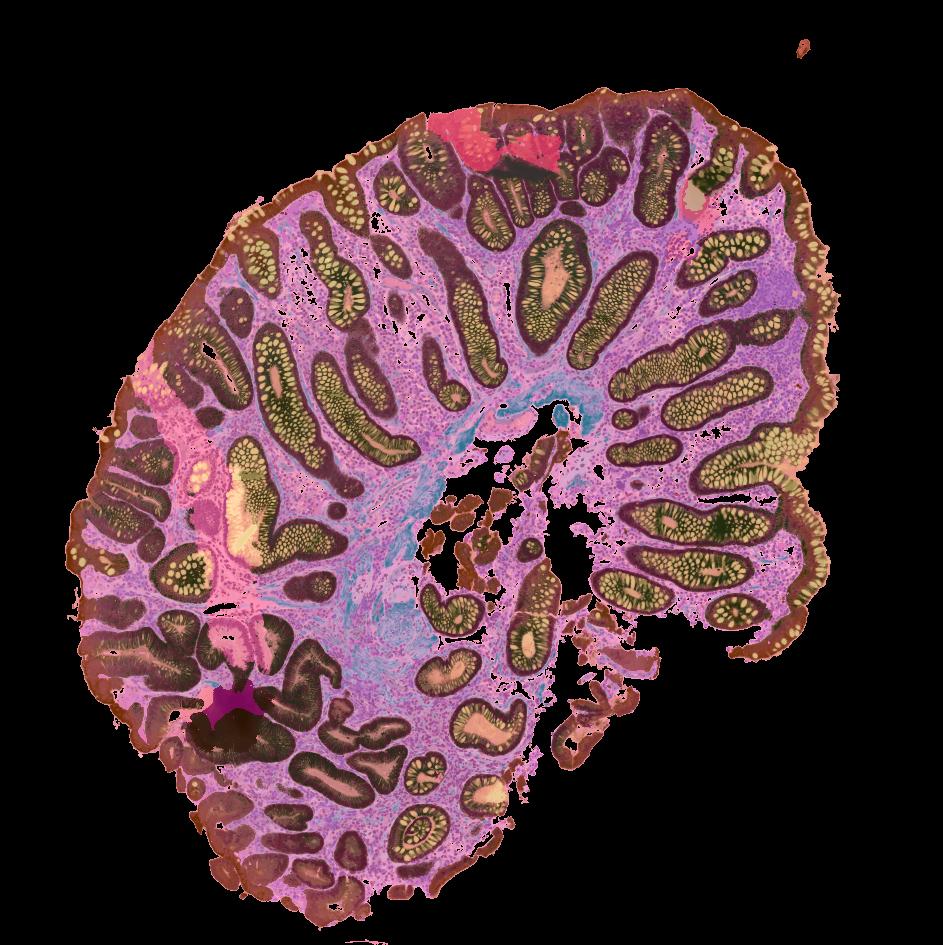

Colorectal cancers (CRCs) arise from precursor polyps whose cellular origins, molecular heterogeneity, and immunogenic potential may reveal diagnostic and therapeutic insights when analyzed at high resolution. We present a single-cell transcriptomic and imaging atlas of the two most common human colorectal polyps, conventional adenomas and serrated polyps, and their resulting CRC counterparts. Integrative analysis of 128 datasets from 62 participants reveals adenomas arise from WNT-driven expansion of stem cells, while serrated polyps derive from differentiated cells through gastric metaplasia. Metaplasia-associated damage is coupled to a cytotoxic immune microenvironment preceding hypermutation, driven partly by antigen-presentation differences associated with tumor cell-differentiation status. Microsatellite unstable CRCs contain distinct non-metaplastic regions where tumor cells acquire stem cell properties and cytotoxic immune cells are depleted. Our multi-omic atlas provides insights into malignant progression of colorectal polyps and their microenvironment, serving as a framework for precision surveillance and prevention of CRC.